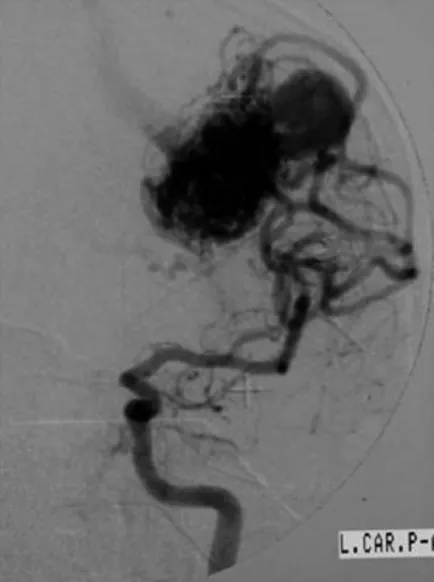

值得注意的是,此次检查同时意外发现左侧顶叶深部合并一处动静脉畸形。患者本人无2型神经纤维瘤病的临床表现,家族史中也无相关记录。

面对体积较大的肿瘤,治疗团队制定了手术切除联合放射外科的阶梯化治疗方案。患者首先接受了左侧听神经瘤的部分切除手术。术中由于合并动静脉畸形导致静脉压持续升高,止血操作极为困难,肿瘤未能实现全切。手术结束后,针对残余病灶采用伽玛刀立体定向放射外科治疗,处方剂量15 Gy,脑干区域受量严格控制在9 Gy以内。术后六个月,患者再次接受伽玛刀治疗,这一次针对的是顶叶深部的动静脉畸形。